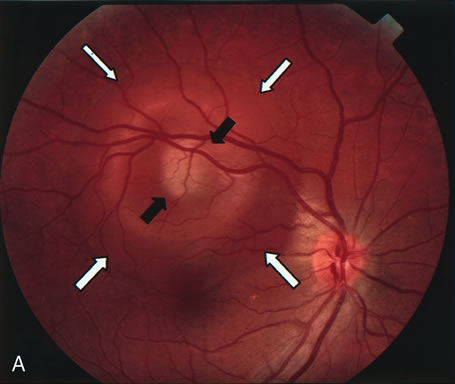

PCV is characterized by the presence of dilated, choroidal vascular channels ending in orange bulging polyp-like dilations in the peripapillary and macular area. Associated features are recurrent subretinal hemorrhage and vitreous hemorrhage, relatively minimal fibrous scarring, absence of retinal vascular disease, pathologic myopia, and signs of intraocular inflammation. FA demonstrates the presence of the dilated vascular channel (Fig. 14 and 15). However, the presence of blood and exudation may block the details of the choroidal circulation on the angiogram. In these cases, ICG angiography can better demonstrate the presence of a distinct network of vessels within the choroid because the larger choroidal vessels are filled with dye.

Fig. 14. A. Color photograph of the right eye shows a ramified pattern of choroidal vascular abnormality irradiating from the peripapillary area toward the macula. The dilated vascular channels end with bulging polyp-like structures. A larger, orange, saccular dilation is seen inferior to the macula (white arrow); leakage of fluid from this vascular abnormality results in serosanguineous pigment epithelium detachment (black arrows). B. The corresponding fluorescein angiogram composite highlights the vascular lesion in the peripapillary area and the serosanguineous detachment of the pigment epithelium that extends inferiorly and temporally off the macula.